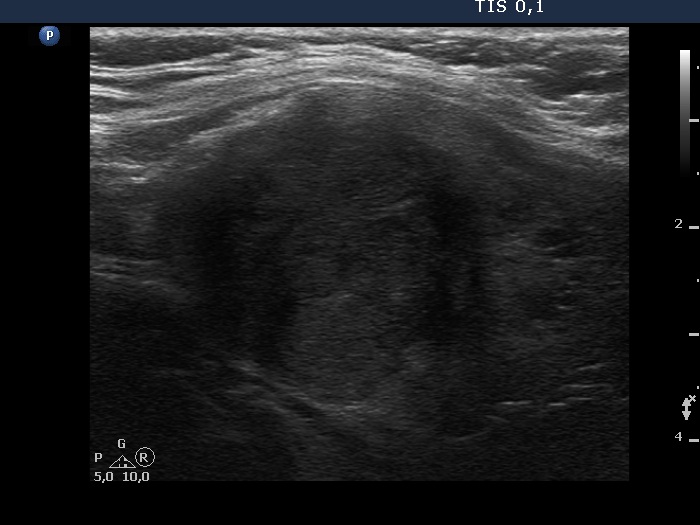

Follow-up examination six years after the first visit (ultrasonographic picture 8)

Upper part of the left lobe, another longitudinal scan.